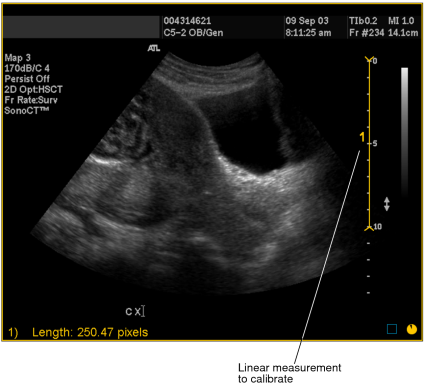

- Select the image that you want to calibrate.

- Draw the line whose length you will use to define the

ratio of pixels-to-centimeters. You should draw this line on a scale

or other element of the image whose length in centimeters is accurately

known. To draw the line, click the Linear Measurement tool

.

. -

Click at the starting point of your measurement and drag. Release the mouse button at the end of your measurement.

A numbered measurement line appears, and the corresponding length appears in the bottom left corner of the viewport. Notice that the length is displayed in pixels.